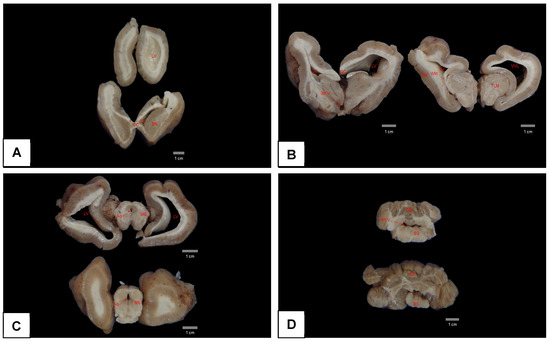

- Carvalho, V.L.; Groch, K.R.; Catão-Dias, J.L.; Meirelles, A.C.O.D.; Silva, C.P.N.; Monteiro, A.N.B.; Díaz-Delgado, J. Cerebral and cardiac congenital malformations in neonatal West Indian manatees (Trichechus manatus). J. Comp. Pathol. 2019, 166, 29–34. [Google Scholar] [CrossRef]